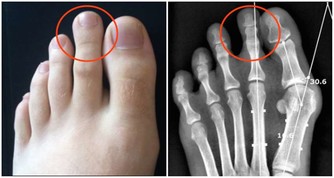

10.手腳發麻

糖尿病、痛風、老年人大腦缺血等很多原因都可以引起晨起手腳發麻,這類人應及時到醫院診治。

但如果年齡尚輕就出現手腳發麻的情況,就要考慮下列可能:

①長時間睡眠姿勢不正確,如枕頭過高導致頭頸偏斜或睡覺時壓著手臂,

建議這類人選擇7~9公分高、軟硬適中的枕頭,並住意睡姿,多翻身,

就可避免頸椎局部血管和神經組織受壓,減少手麻症狀;

②長期伏案工作會導致頸椎病,引起晨起時手腳發麻,可通過中醫按摩、理療、針灸、牽引等治療;

③缺乏維生素B1也會引起手發麻,這類人要糾正偏食的不良習慣,多吃雜糧、豆類,補充維生素B1。